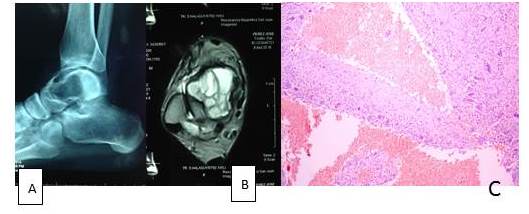

A. Estudio radiológico. B. hematoxilina-eosina. C Aumento 40X

Los tumores osteogénicos malignos, constituyeron 16 casos de los cuales 15 casos (94 %) correspondieron a osteosarcoma convencionales, (Figura 3) y un caso (6 %) osteosarcoma de células pequeñas y presentaron la siguiente distribución: 11 casos (68,75 %) pertenecientes al sexo masculino y 5 casos (31,25 %) sexo femenino, respecto al grupo etario 9 casos (56 %) se ubicaron en rango de 11-20 años, seguidos de 3 casos (18,75 %) en el grupo de 0-10 años.